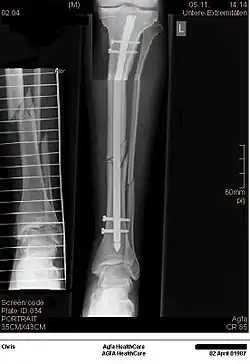

Verriegelungsnagel

Die genannten Probleme führten (zunächst etwas zögerlich, da die Arbeitsgemeinschaft für Osteosynthesefragen (AO) sich zu dieser Zeit nahezu ausschließlich mit der Systematisierung der Plattenosteosynthese befasste) zur Entwicklung des Verriegelungsnagels. Dieser wurde zunächst noch in hergebrachter Weise formschlüssig eingebracht und mittels mehrerer proximal und distal quer eingesetzter Verrieglungsbolzen fixiert. Dies löste das Problem des Längenverlustes und des Rotationsfehlers.

Die nächste Stufe der Weiterentwicklung war der unaufgebohrte Verriegelungsnagel (UTN = unaufgebohrter Tibianagel, UFN = u. Femurnagel). Diese Nägel bestehen mittlerweile aus massiven Titanlegierungen, sind deutlich dünner als der Durchmesser der Markhöhle und schädigen somit nicht die Durchblutung im Frakturbereich. Durch winkelstabiles Einbringen der Verriegelungsbolzen auch am äußersten Nagelende lassen sich jetzt sogar gelenknahe Stückbrüche hiermit versorgen.

Verriegelungsnägel gibt es nunmehr auch für den Oberarm, diese können je nach Fraktur von proximal (Schulter) oder distal (Ellbogen) eingebracht werden (UHN = u. Humerusnagel).